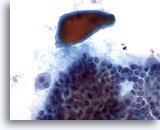

Verdenking van maligniteit

Als het monster niet hypercellulair is of als de hierboven beschreven kenmerken voor papillair en medullair carcinoom of andere maligniteit niet allemaal aanwezig zijn, wordt dit gerapporteerd als verdacht voor maligniteit. De positieve voorspellende waarde (maligniteitsfrequentie bij histologie) van ” verdenking van papillair carcinoom” varieert in de literatuur van 54 tot 84%. Dit is ervan afhankelijk of een andere minder doorslaggevende categorie, zoals onbepaald, in het schema is opgenomen. [7, 8, 9, 10] Als een onbepaalde categorie wordt toegevoegd aan de verdachte categorie, is de positieve voorspellende waarde voor de verdachte categorie 64% of hoger. [7, 9, 10] Omdat andere soorten carcinoom in de schildklier minder vaak voorkomen, wordt hun positieve voorspellende waarde voor een verdachte diagnose niet gerapporteerd.